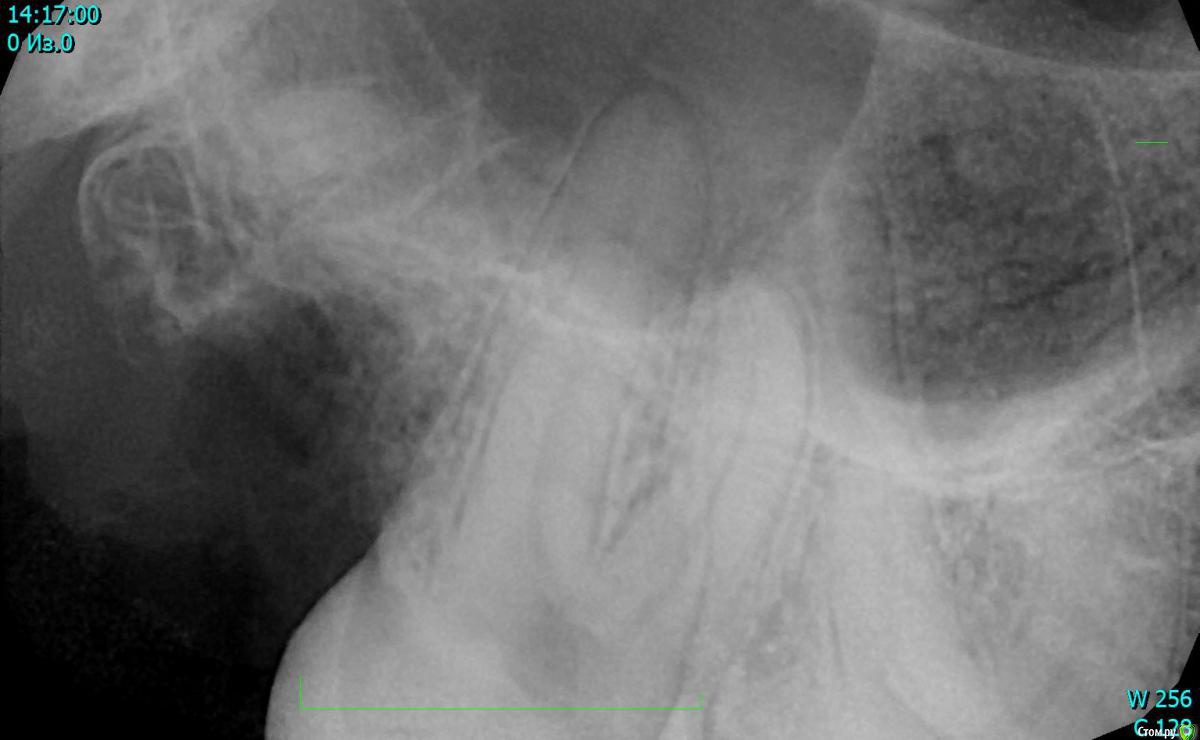

Egor.dentistry Опубликовано 22 января, 2018 Поделиться Опубликовано 22 января, 2018 (изменено) Ничего не предвещало беды, самое рядовое удаление зуба 18. В результате отлом верхушки дистально-щечного корня. Попытка ее достать закончилась проталкиванием в синус, откинул лоскут, визуализация была ограничена, ушился назначил медикаментозную терапию,направил в ЧЛХ. Как вы решаете данные осложнения в своей практики? Если таковые встречаются) Изменено 22 января, 2018 пользователем Egor.dentistry 1 Ссылка на комментарий

Egor.dentistry Опубликовано 22 января, 2018 Автор Поделиться Опубликовано 22 января, 2018 я бы не полез за ним ))Теперь к ЛОРам на эндоскоп)) согласен с вами, но фрагмент достаточно большой, ни 2 мм, он визуализировался, даже подцепил..... Ссылка на комментарий

Egor.dentistry Опубликовано 22 января, 2018 Автор Поделиться Опубликовано 22 января, 2018 Лучше всего не проталкивать)) Если корень отломился, сразу пытайтесь визуализировать фрагмент глазами. В вашем случае я бы сначала попытался подцепить фрагмент файлом. Если нет, то отслоился бы и достал корень сбоку. А теперь, наверное, только к ЛОРуЗондом его цеплял, подвижен был. Латеральным доступом было бы надежнее, не успел( Ссылка на комментарий

Egor.dentistry Опубликовано 22 января, 2018 Автор Поделиться Опубликовано 22 января, 2018 В прошлом месяце также протолкнул, но от 7 зуба))Открылся, окно как для синуса, микрозеркалом его нашел, отсосом вытащил, вит цт перекрыл все))В области 16,17, также бы поступил, в данном случае не рискнул, очень плохой обзор был. Ссылка на комментарий

StomV Опубликовано 22 января, 2018 Поделиться Опубликовано 22 января, 2018 Недавно тоде протолкнул при удалении 6, благо он болтался на гранулеме,немного расширил отверстие в лунке и выковырял его. А если в области 8 проталкивается,думаю самое разумное,это сделать окно латеральное и попытаться достать его,но думаю без нормального увеличения и света,это сделать проблематично. Ссылка на комментарий